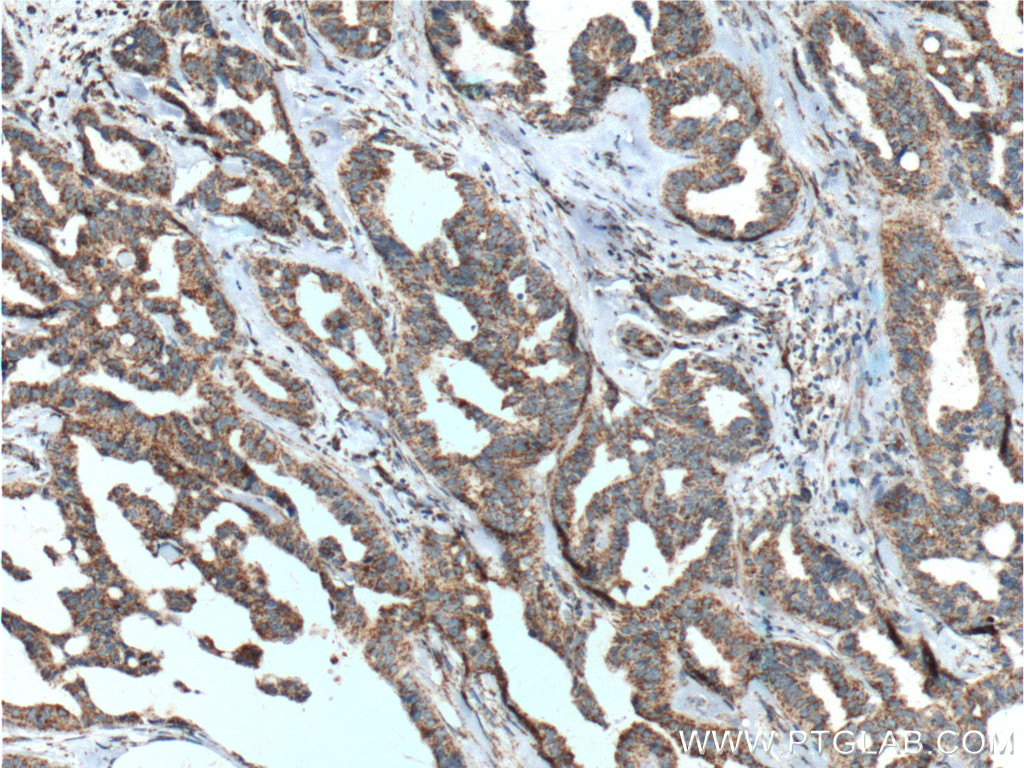

| Positive IHC detected in | human prostate cancer tissue, human breast cancer tissue Note: suggested antigen retrieval with TE buffer pH 9.0; (*) Alternatively, antigen retrieval may be performed with citrate buffer pH 6.0 |

| Immunohistochemistry (IHC) | IHC : 1:50-1:500 |